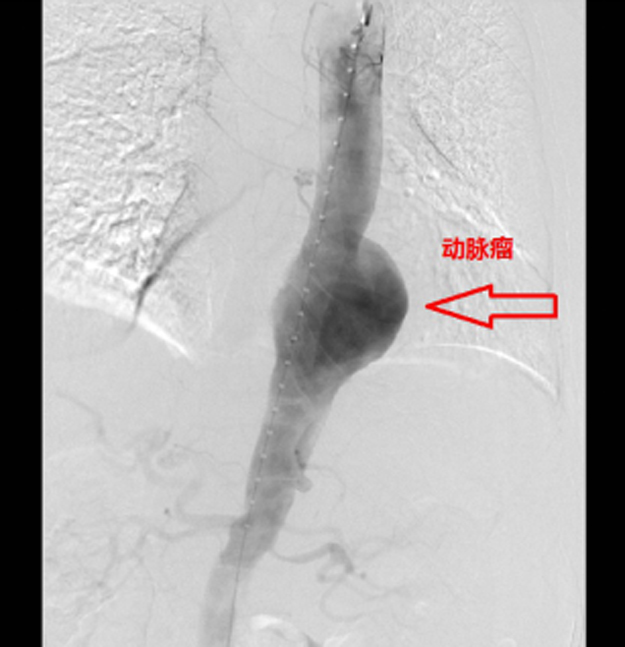

人体“不定时炸弹”——主动脉瘤

主动脉瘤是以主动脉某段局限性退化扩张,最终无法承受血流冲击导致瘤壁破裂的一种高危性疾病,90%以上的破裂者发生猝死。一旦主动脉瘤发生破裂,高速、高压的动脉血立即喷射入腹腔,在短短几分钟患者失血达到数千毫升,随即出现休克,因大出血而死亡。只要破裂口出现在腹腔内,任何抢救和输血都是徒劳的,所以,临床医生把这种凶险的疾病戏称为“不定时炸弹”,这意味着只要发现主动脉瘤,就相当于带上一个不定时的炸弹,随时随地就可能破裂要命。在最近的流行病学调查中,发现得到诊断的症状性主动脉瘤中,2年内自然破裂率达到50%。